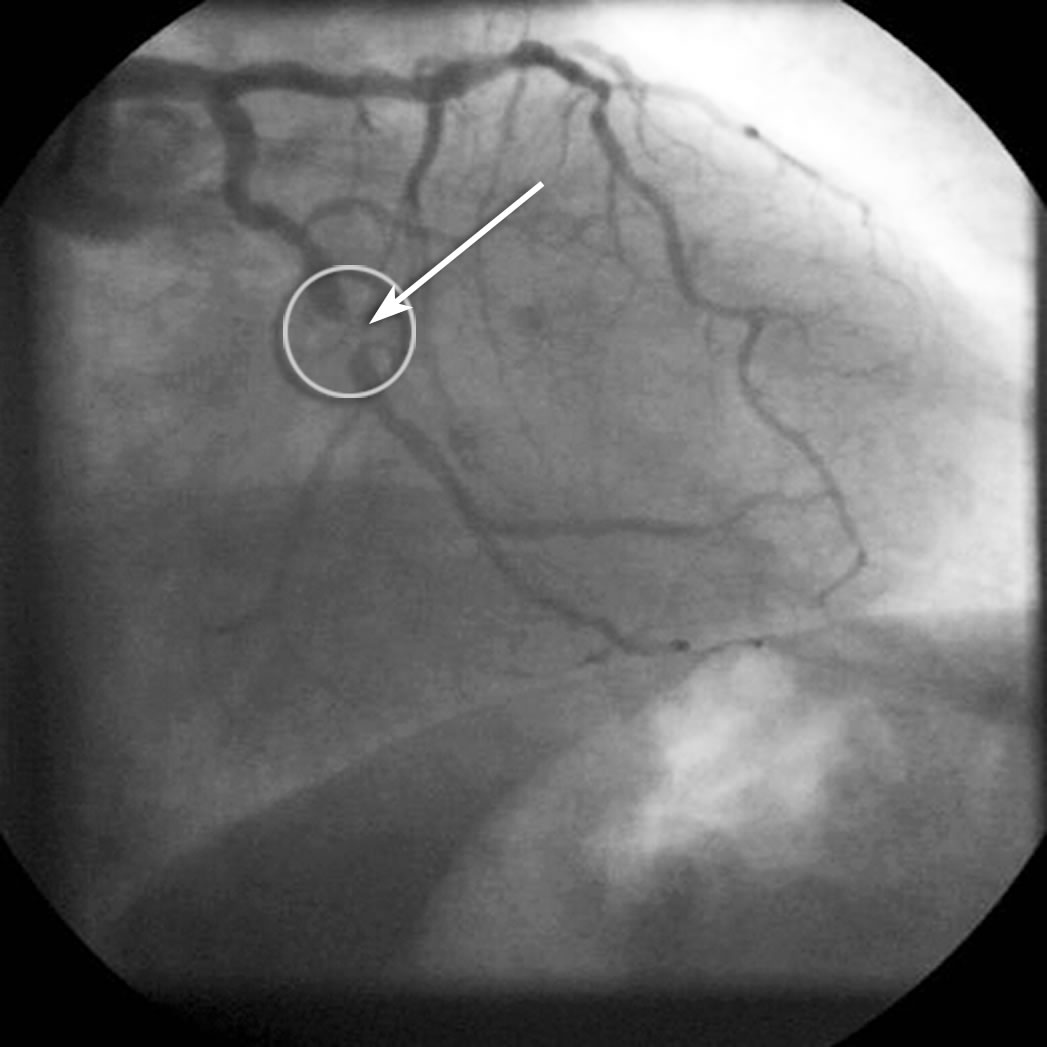

geringe Einengung hochgradige Einengung

Abb. 22 Abb. 23

Herzkatheterdarstellungen von 2 Verengungen:

Abb. 22: Geringe Einengung

Abb. 23: Hochgradige Einengung, das Gefäß wirkt nahezu unterbrochen!

1. Eine Myokardszintigraphie wird nach einer Katheteruntersuchung durchgeführt und zwar dann, wenn man das Ausmaß einer Verengung nicht sicher erkennen kann:

In vielen Fällen wird man bei einer Herzkatheteruntersuchung Einengungen finden, die entweder nur minimal (Abb. 22 links) oder die hochgradig (Abb. 22 rechts) sind.

In diesen Fällen ist ein Zusammenhang mit den Beschwerden eines Menschen eindeutig: Geringe Verengungen sind für die Beschwerden sicherlich nicht verantwortlich, hochgradige Verengungen sind eindeutig verantwortlich. In einigen Fällen findet man aber Verengungen, die die Kardiologen als „grenzwertig“ einstufen, weil sie weder eindeutig hochgradig noch eindeutig unbedeutsam sind (Abb. 23).

mittelgradige Einengung

Abb. 23

Man kann solche Verengungen nicht auf den Millimeter genau ausmessen und letztendlich entscheidet auch nicht das Aussehen des Gefäßes, sondern seine Fähigkeit, Blut in ausreichender Menge zu transportieren.

Bei solchen grenzwertigen Verengungen führt man eine Myokardszintigraphie durch, um zu prüfen, ob die Arterienverengung bereits zu einer Durchblutungsstörung führt oder nicht. Diese Frage ist von großer Bedeutung, denn wenn eine Durchblutungsstörung besteht dann kann man überlegen, ob eine weitere Behandlung mittels Ballonerweiterung (PTCA) oder Operation notwendig ist; verursacht die Verengung aber keinerlei Durchblutungsstörung macht die Durchführung einer PTCA oder Bypass-Operation wenig Sinn. Hier dient die Szintigraphie also dazu, die funktionelle Bedeutung der Verengung zu klären und um zu entscheiden, wie die weitere Behandlung aussehen sollte.